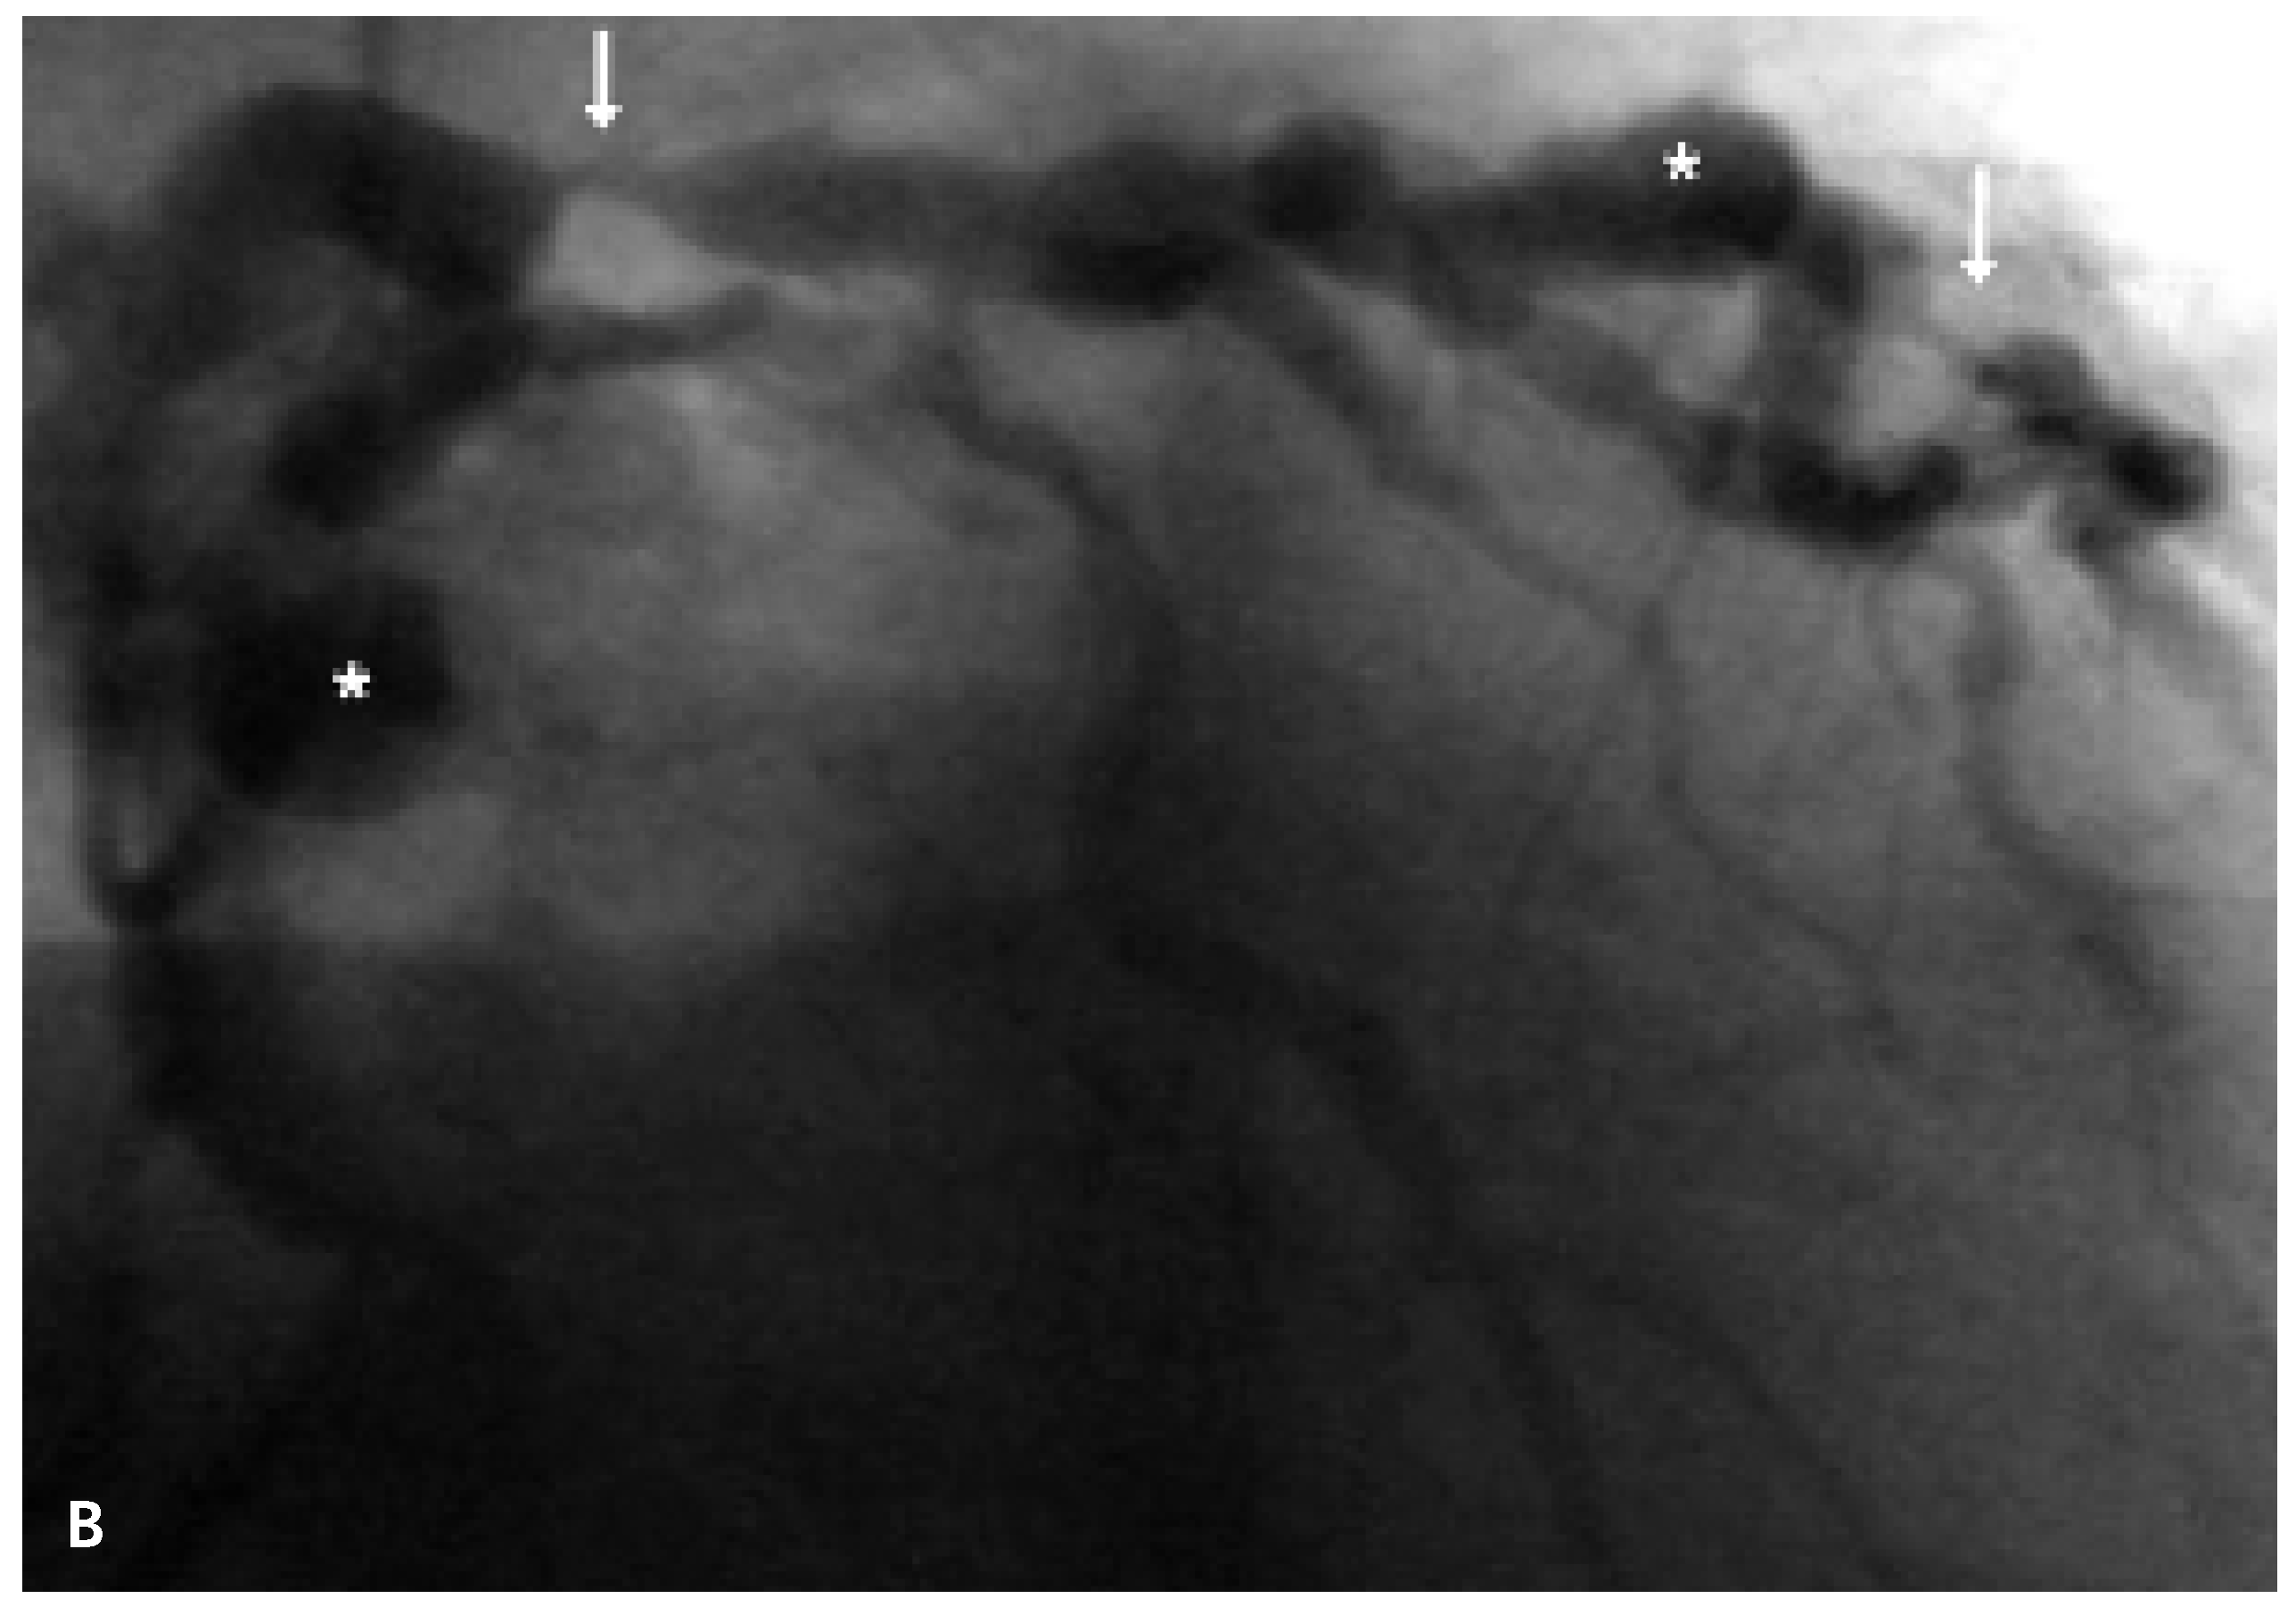

Severe Coronary Artery Ectasia and Abdominal Aortic Aneurysm

Case Report